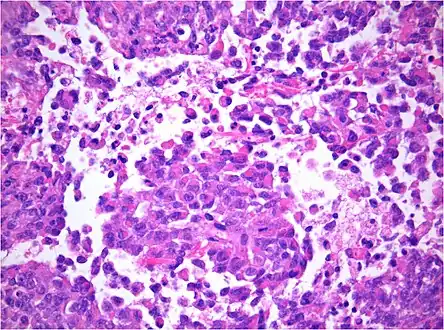

AT/RT and rhabdoid tumor share the term "rhabdoid" because under a microscope, both tumors resemble rhabdomyosarcoma.

AT/RT Histology with numerous rhabdoid tumor cells

Histology

The tumor histopathology is jumbled small and large cells. The tissue of this tumor contains many different types of cells including the rhabdoid cells, large spindled cells, epithelial and mesenchymal cells, and areas resembling primitive neuroectodermal tumor (PNET). As much as 70% of the tumor may be made up of PNET-like cells. Ultrastructure characteristic whorls of intermediate filaments are seen in the rhabdoid tumors (as with rhabdoid tumors in any area of the body). Ho and associates found sickle-shaped embracing cells, previously unreported, in all of 11 cases of AT/RT.[18]